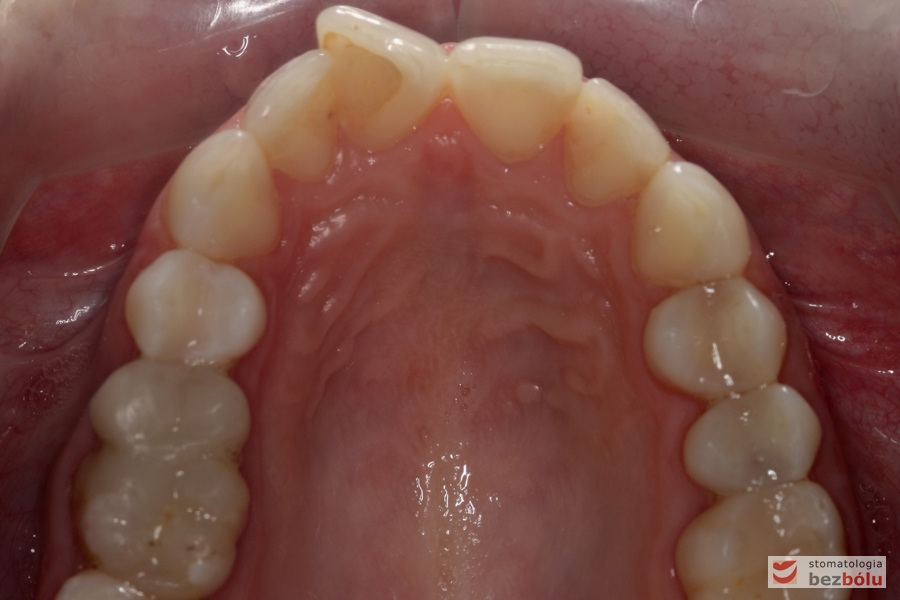

Diagnostyka – nieregularna linia dziąsła, proporcje zębów ~85%

Zwężenie szczęki - brak "piątki" po stronie prawej, mezjalizacja sektora bocznego na skutek stłoczeń trzeciorzędowych

Zwężenie szczęki – brak „piątki” po stronie prawej, mezjalizacja sektora bocznego na skutek stłoczeń trzeciorzędowych